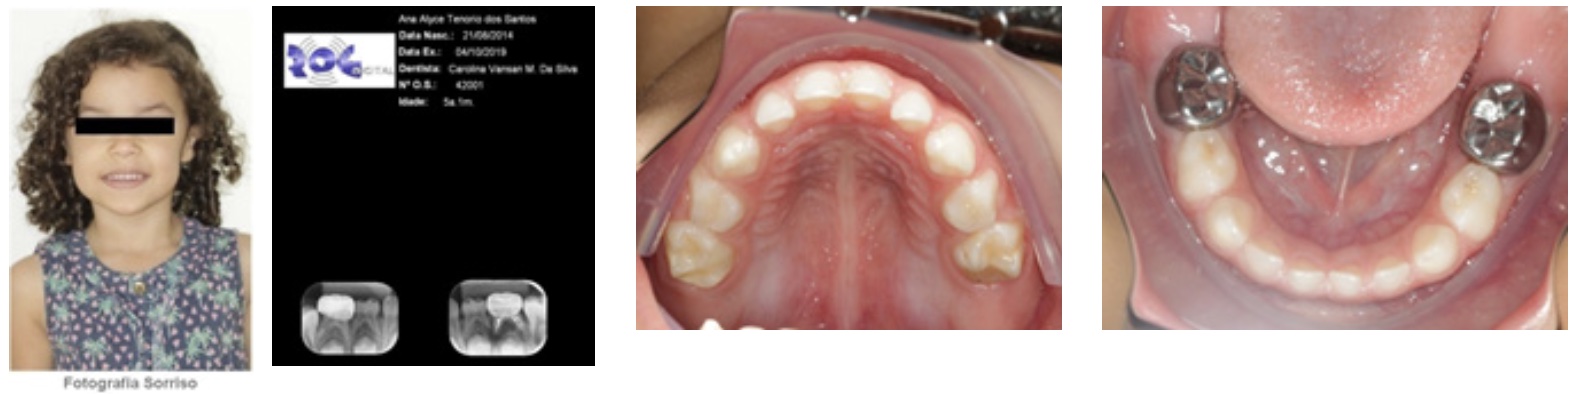

Ha sido estudiado el caso de dos niñas de 5 años, gemelas, univetelinas idénticas que poseían el mismo patrón de HMD en los dientes 55,65, 75 y 85, que ya se encontraban con alto grado de destrucción. En la gemela 1, se ha constatado lesión de caries en los dientes 85, 75 y 65 (Figura 1). Por otra parte, en la gemela 2, la lesión se concentraba en los dientes 55 y 65 (Figura 2). Además, se observó en ambas gemelas un histórico de sensibilidad en los dientes 55 y 65, seguido de incomodidad provocada durante el cepillado de dientes. Se observó, también, que la destrucción coronal en los segundos molares superiores de las niñas era consecuencia de las fracturas con la exposición dentinaria y acumulación de biofilm que ocasionan lesiones cariosas.

Figura 2: Gemela 2: Imagen clínica y radiológica sacadas al iniciar el tratamiento. Se observa: en la imagen A, la fotografía de la sonrisa; en la B, radiografías periapicales; en la figura C, imagen vestibular de los dientes superiores e inferiores; las imágenes D y E muestran imágenes intrabucales de las superficie oclusales de las arcadas inferiores y superiores. Asemás, Se ve los dientes 55 y 65 con hipoplasia